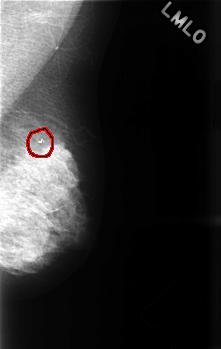

C_0486_1.LEFT_MLO

LEFT_MLO LINES 4536 PIXELS_PER_LINE 2864 BITS_PER_PIXEL 12 RESOLUTION 50 OVERLAY

FILE: C_0486_1.LEFT_MLO.OVERLAY

TOTAL_ABNORMALITIES 1

ABNORMALITY 1

LESION_TYPE CALCIFICATION TYPE PLEOMORPHIC DISTRIBUTION CLUSTERED

ASSESSMENT 4

SUBTLETY 5

PATHOLOGY BENIGN

TOTAL_OUTLINES 1

BOUNDARY